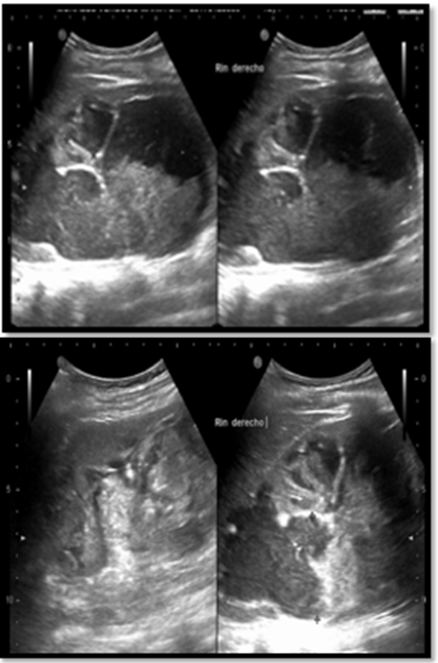

Presentamos el caso de una paciente femenina de 19 años de edad cursando las primeras horas de puerperio fisiológico de su I embarazo intrauterino, descrito de curso normoevolutivo. Se presenta a urgencias por dolor abdominal y hematuria macroscópica holomiccional de 24 horas de evolución, a la exploración física hemodinámicamente estable con dolor a la palpación profunda de flanco derecho sin datos de irritación peritoneal, se confirma la presencia de hematuria con coagulos amorfos. Se realiza ultrasonido abdominal encontrando lesión heterogénea en riñón derecho (ver Figura 1). Se solicita tomografía abdominal con contraste intravenoso, en la que se aprecia imagen sugestiva de hematoma contenido en riñón derecho (ver Figura 2) debido a deterioro hemodinámico abrupto se decide realizar nefrectomía derecha. En la Figura 3 se aprecia la imagen de la pieza quirúrgica, El reporte de patología descarta la presencia de angiomiolipoma u otras neoplasias renales.

Figura 1 US renal

El ultrasonido suele ser el primer estudio realizado en estos pacientes encontrando la imagen característica de hematoma perirrenal. el estado hemodinámico dictará la obtención del estudio de imagen de elección: La tomografía axial computarizada (TAC) con contraste intravenoso, con una sensibilidad estimada de 100%.7,8,11. En la TAC la detección de una tumoración en presencia de hemorragia perirrenal es límitada sin el contraste intravenoso, en casos en los que no es posible contar con este estudio, la resonancia magnética (RM) puede ser una alternativa, la angiografía puede ser de utilidad en el diagnóstico de enfermedad vascular especialmente en casos en los que sea factible una angioembolización.4